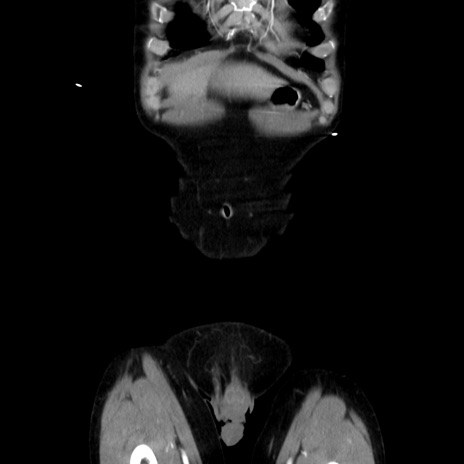

症例37(冠状断像)

【症例】40歳代 男性

【主訴】腹痛

【現病歴】4時間ほど前に電車に乗車中に臍部上より腹痛出現。徐々に増悪し起立困難となり、救急外来受診。生ものは数日食べていない。今朝お雑煮を食べた。

【身体所見】BT 36.8℃、BP 117/84mmHg、HR 91/min、SpO2 97%、苦悶様、腹部:臍上部広範囲圧痛あり、反跳痛±

【データ】WBC 8100、CRP 0.03